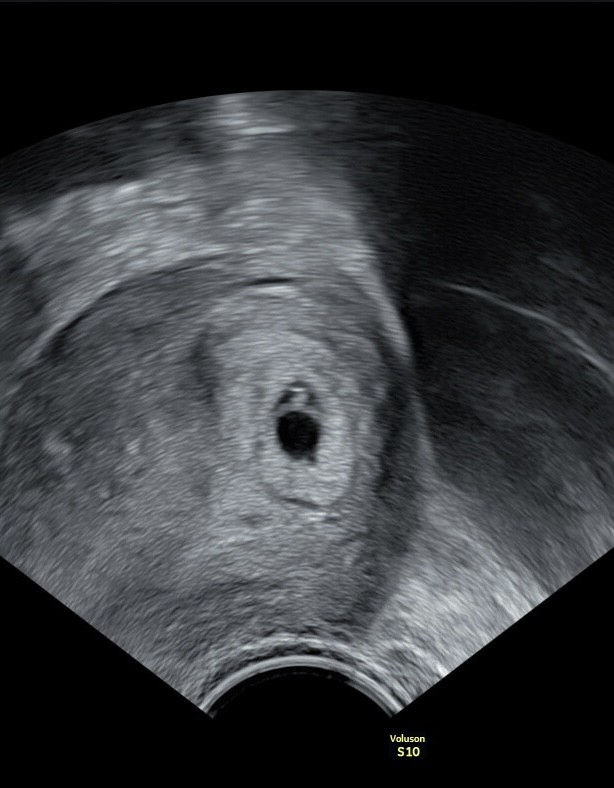

Dzis mialam usg na ktorym widać bylo serduszko dziecka. Wszystko fajnie ale okazało się że zarodek jest bardzo mały bo ma tylko 2,5mm (powinnam być na końcówce 7tc ale przez ostatnie nieregularne cykle może to być też 6tc). Czyli jest za maly jak na wiek ciazy.

Dodatkowo pęcherzyk żółtkowy jest duży przez co lekarz nie dał mi szans na tą ciąże.